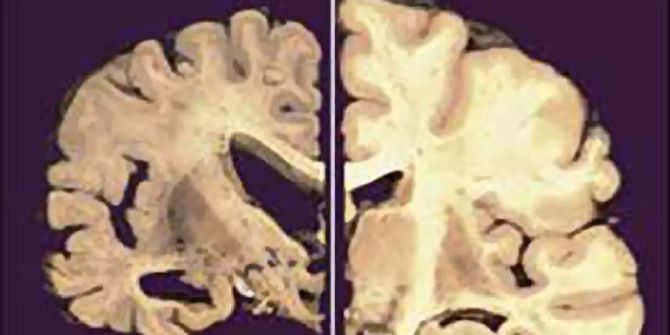

Die Zusammenarbeit zwischen Evotec und der Bristol Myers Squibb hat im Jahr 2016 begonnen. Ziel ist es, krankheitsmodifizierende Behandlungen für ein breites Spektrum von neurodegenerativen Erkrankungen zu identifizieren. Mit der gemeinsamen Forschung intensivieren Evotec und «BMSC» die Alzheimer-Forschung.

Bisher zugelassene Medikamente würden nur eine kurzfristige Behandlung der Symptome bieten. Weiter bestehe ein enormer ungedeckter medizinischer Bedarf an Therapien, die die Krankheit verlangsamen oder umkehren.